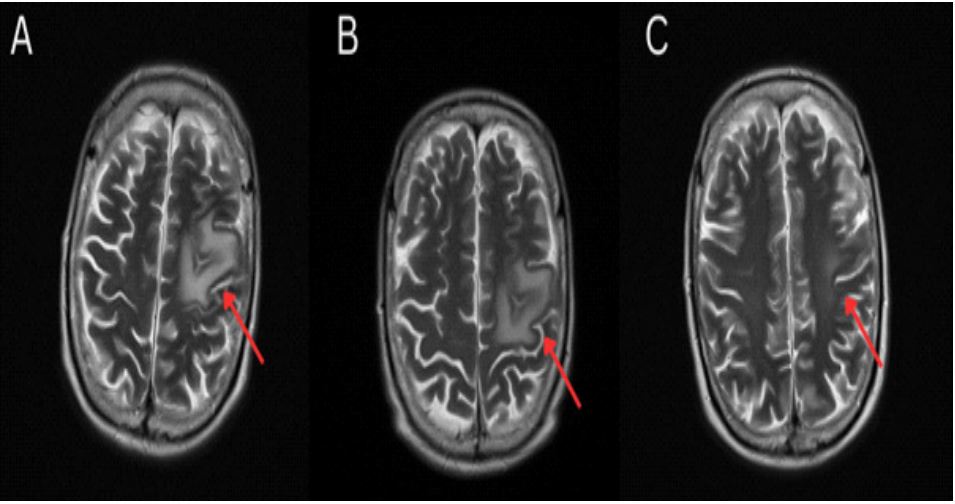

On review in the ED, his Glasgow Coma Scale (GCS) was 15/15, however he demonstrated right upper and lower limb weakness (recorded as 3.5 out of 5 by the reviewing doctor), marked slurring of speech, as well as ecchymosis to upper lip at the trauma site. This gentleman had no recollection of precipitating events, however fortunately he had no signs of major head trauma or cranial fracture. On admission he underwent Computed Tomography (CT) of the brain with contrast which demonstrated thickening of the cortex in the left frontal region, with associated vasogenic edema and enhancement extending into the sulci, with local mass effect but no evidence of intracranial hemorrhage or ischemia nor herniation (Figure 1). There was mucosal opacification of left ethmoid and maxillary paranasal sinuses with slight nasal septum deviation to the right on CT brain consistent with the history of epistaxis.

Figure 1: CT Brain with contrast demonstrated thickening of the cortex in the left frontoparietal region, with associated vasogenic edema and enhancement extending into the sulci, with localised mass effect but no herniation.